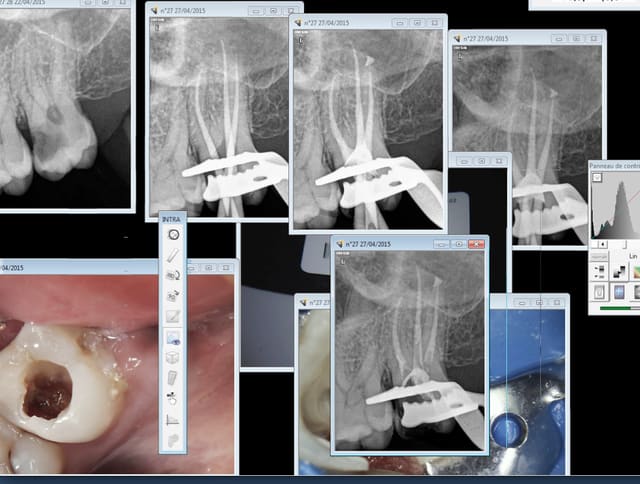

Chacun son toc, moi c'est les radios en endo je peux en faire jusqu'à une douzaine. je les garde pas toutes hein.

La camera ca devient aussi un toc. -)))))

Toc, toc ca t'énerve les endos ? -)))))

Eh oui des fois il faut s'y reprendre à plusieurs fois, radio cone en place ( fois 2), radio cone scellé en place (fois 2) radio après mac spadden. ouf !

Merde ,encore une abusive, j'aurais du faire un coiffage à la biodentine.

Tiens casa pour te faire plaisir. 1 mm de r25 pété sur cette 27. Quand on réutilise le matos censé ne servir qu'une fois pour cause de paiement au lance pierre du donneur d'ordre voilà ce qui arrive ( j'avais pourtant pris mes précautions (cathétérisme) sur cette dent de rhinocéros ultra longue)

Quelqu'un connait un endo exclusif pour aller chercher le morceau pété ? -))))